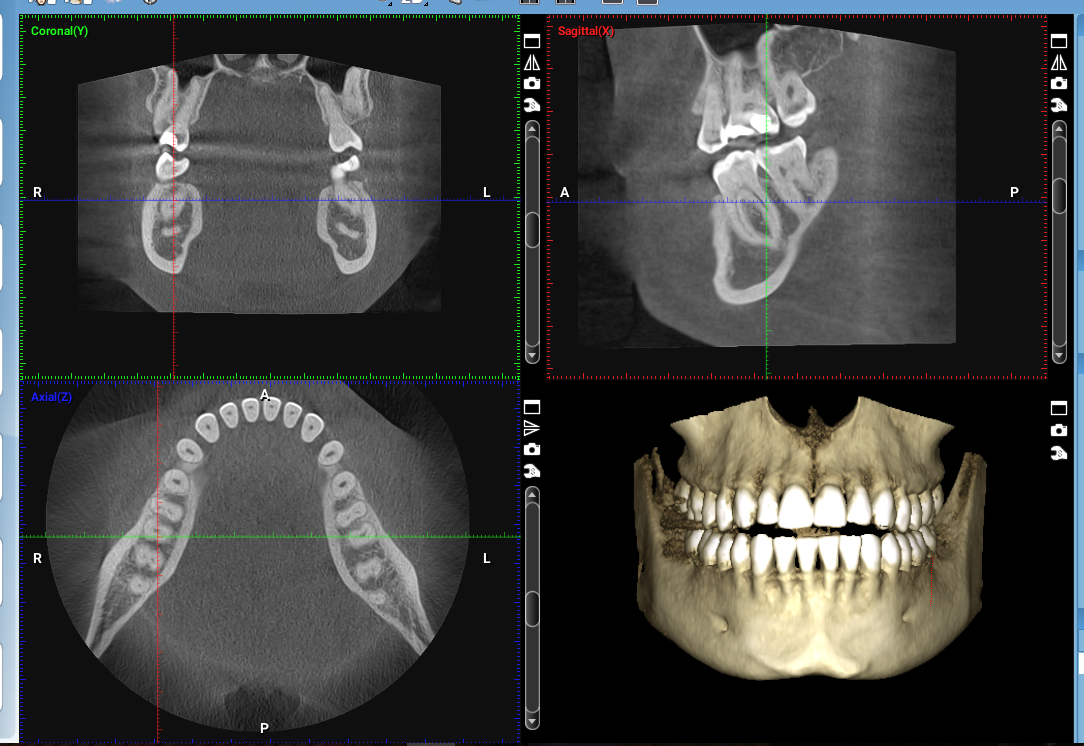

Investigaţia CBCT se realizează cu ajutorul unei singure rotații de 360°, în jurul capului pacientului, în urma căreia se obţin peste 300 de imagini ce construiesc computerizat imaginea finală, tridimensională. Informațiile 3D sunt preluate la scara 1:1, ceea ce permite vizualizarea în amănunt a detaliilor importante pentru medicul stomatolog.

Cu ajutorul programelor software, imaginile pot fi manipulate pentru a arăta diverse unghiuri, se pot măsura adâncimi, grosimi, densităţi.

De asemenea, se poate simula computerizat efectuarea de intervenţii chirugicale de implantologie orală sau evoluţia tratamentelor ortodontice.